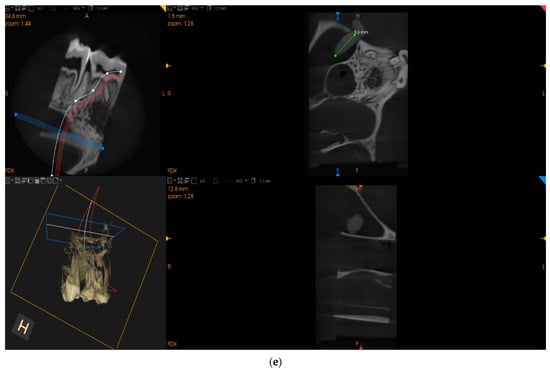

| 1 | 10.6 | no | no | yes |

| Balloon Sinus Elevation | 11.00 | 1.16 | 10.65 | 9.80–13.30 |